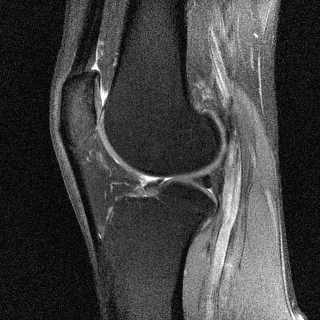

T1-weighted MRI images present a good contrast between fat, which appears dark, and water, which appears brighter. This type of contrast is used, for instance, in brain imaging to distinguish gray matter from white matter. Pathologies are often revealed by T2-weighted MRI. Edemas (abnormal accumulation of fluids) appear bright, while tumors often appear darker than normal tissues.

Examples of T1 and spin-density weighted images are shown in Figure 2.10.